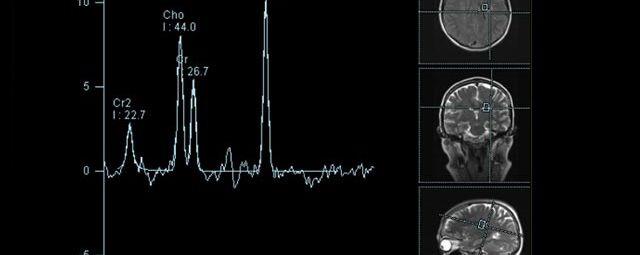

Spezialtechniken der Magnetresonanz

• MR-Spektroskopie

Diese Verfahren werden bei verschiedenen Fragestellungen in verschiedenen Körperregionen in die Messprotokolle sinnvoll eingefügt. Teilweise können dadurch Differenzierungenverschiedener krankhafter Prozesse verbessert werden.

• Tumore, ggf. mit Spektroskopie